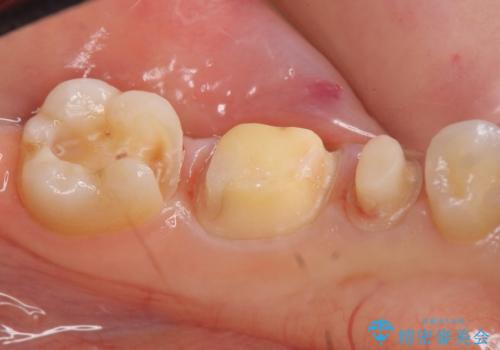

- 左下奥歯の銀歯が気になると来院された方の症例です。

左下7はセラミックインレーによる修復を行い、左下5、6はオールセラミッククラウンによる補綴を行いました。

- オールセラミッククラウン…¥100,000×2、仮歯…¥10,000×2、ファイバーコア…¥20,000、セラミックインレー…¥70,000費用は治療当時の料金となります